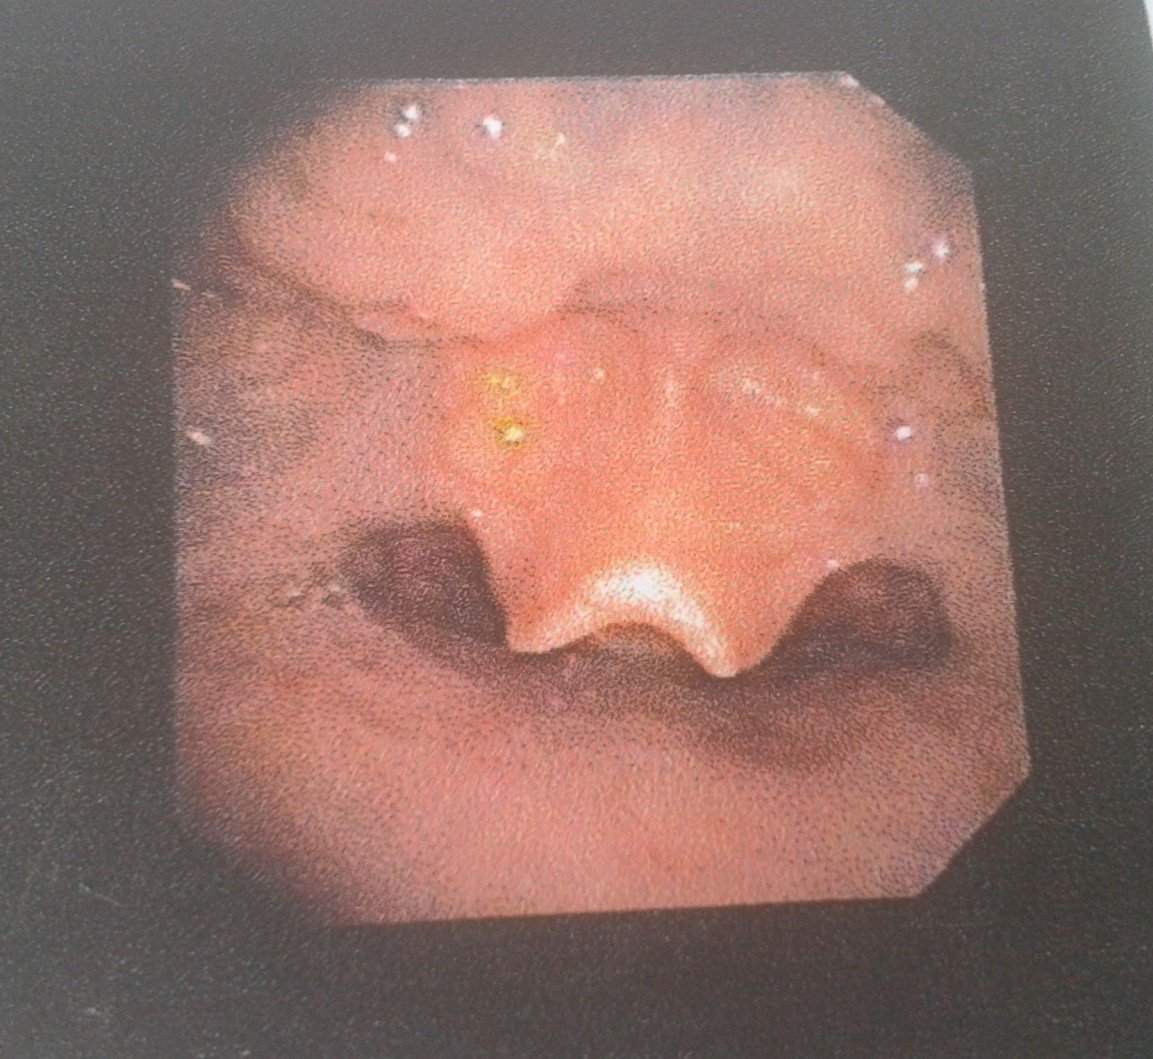

咽喉壁及舌根部淋巴滤泡增生怎么治疗,求专家

像您这种情况可以用激光治疗 将咽后壁以及舌根部滤泡清除饥挡涌 有助于改善咽部的异物感 同时可以进行雾化吸入治疗 平时注意禁食辛辣 煎炸 容易上火否了的食物室崭 避免熬夜劳累,希望对您能有帮助